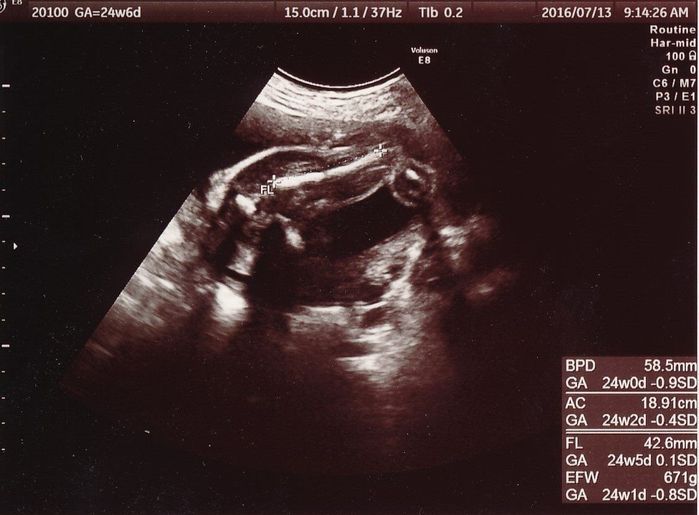

妊娠24週目のエコー写真

大腿骨の長さ(FL)から赤ちゃんの大きさを推定していたようです。推定体重は671gで、順調に大きくなってくれていることが分かります。先天性異常の検査をするかどうか自分なりに色々と考えましたが、1人目のときと同じくやはり見送ることに決めました。